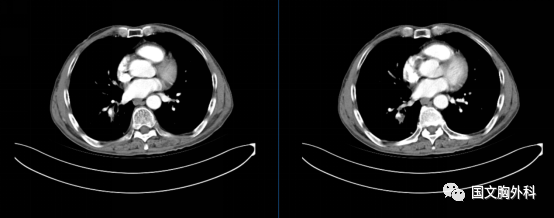

治療后↓

患者于吉林國文醫(yī)院順利完成右肺下葉切除術(shù)手術(shù)治療,保留了右肺的中葉。

更幸運的是原先肺癌切下來后,顯微鏡下都找不到癌細(xì)胞,這真是奇跡。來到國文醫(yī)院診療,真是得病后不幸中的萬幸。